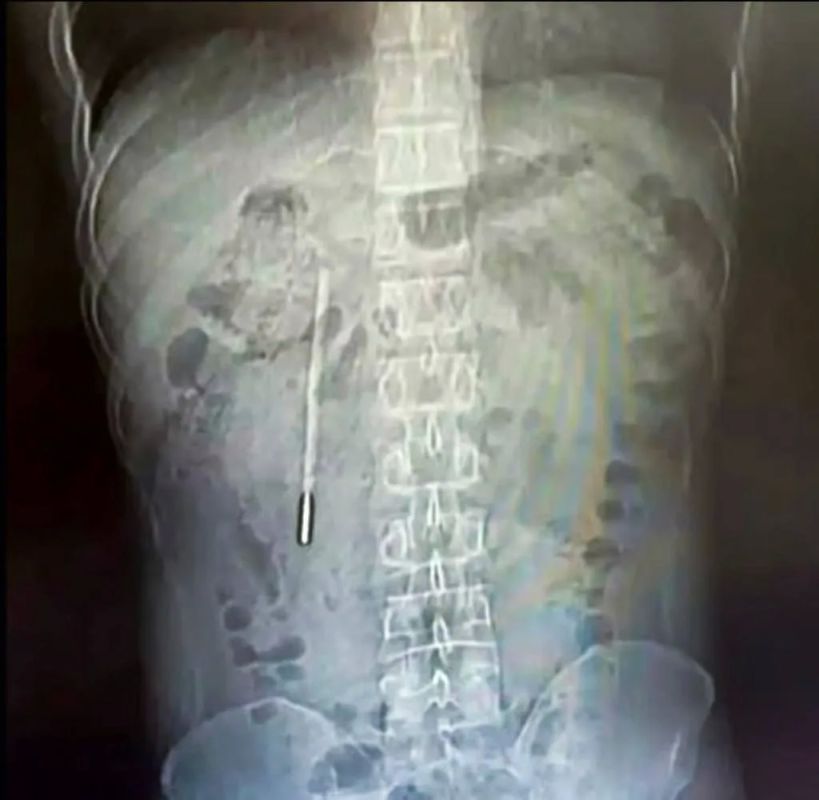

32-летний житель провинции Чжэцзян по фамилии Ван обратился в больницу с жалобами на боли в животе. Обследование показало наличие инородного предмета в двенадцатиперстной кишке — хирурги провели срочную операцию.Оказалось, что причиной болей был...